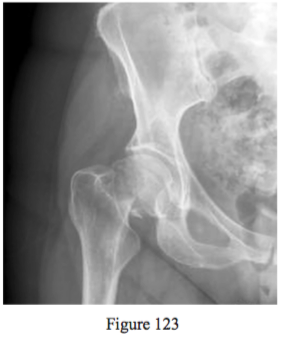

Question 123

Figure 123 is the anteroposterior radiograph of a 69-year-old active woman who fell o of a ladder and is unable to ambulate. Which treatment o ers the best long-term solution?